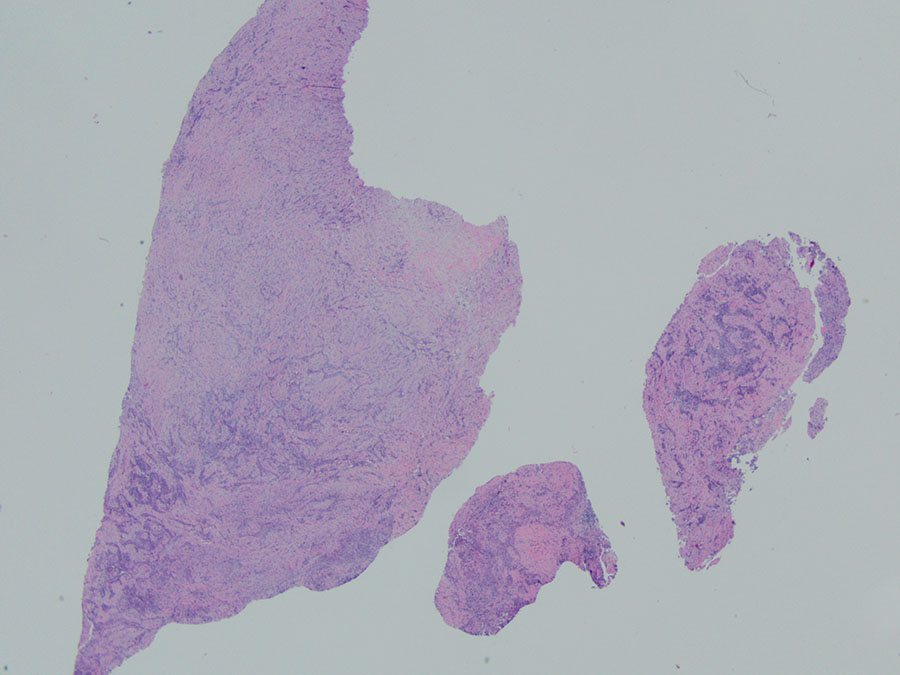

A right video-assisted thoracoscopy was performed and two chest wall biopsies were taken. Fragments of tan-white soft tissue were received, measuring up to 1.8cm in aggregate. Upon histologic evaluation, low-power magnification (2X) revealed a neoplasm with biphasic morphology (Figure 1). Sheets of epithelioid cells were noted within a background of dense fibrosis. Cytologically, the tumor cells appeared monotonous, showing round nuclei with prominent nucleoli. Mitotic figures were inconspicuous (Figure 2). Atypical spindled to ovoid tumor cells were noted in streaming fascicles within dense hyalinized fibrous stroma (Figure 3). The interface of these two patterns is seen in Figure 4. Focal invasion into chest wall fat is noted (Figure 5). The diagnosis was confirmed with positive stains including D2-40, WT-1, calretinin, and pancytokeratin (Figures 6-9). The tumor cells were negative for TTF-1, p40, CEA and CD15.